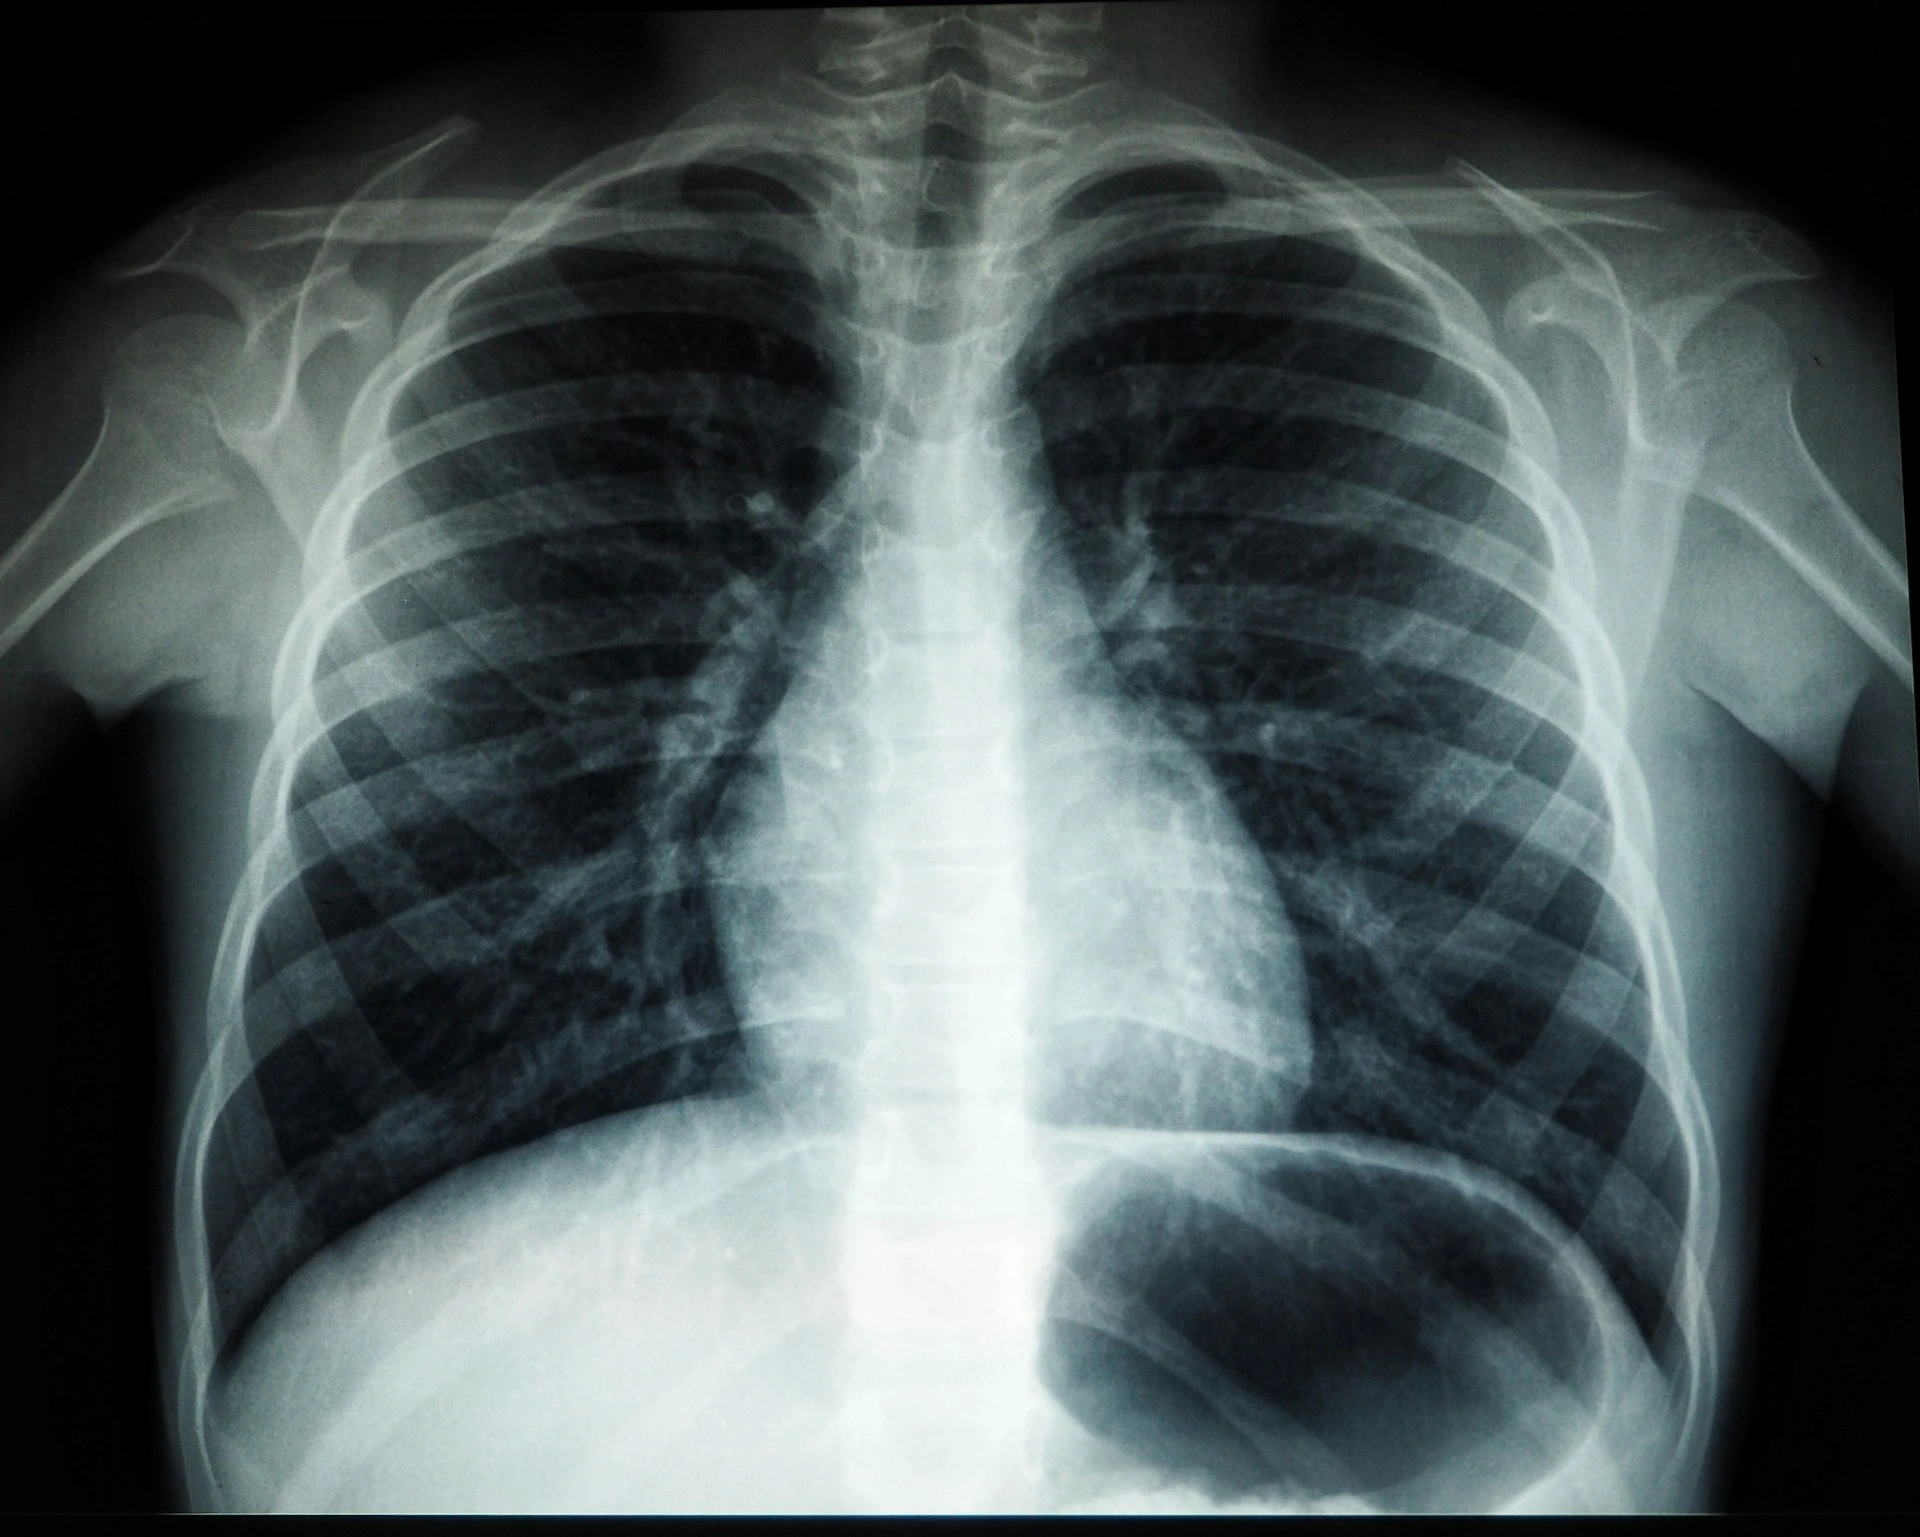

Karena itu, tenaga medis selalu memeriksa posisinya menggunakan teknik klinis ataupun bantuan alat seperti X-ray. Untuk perawatan di rumah, Anda harus mengenali sejak awal tanda NGT masuk ke paru agar tindakan koreksi bisa dilakukan secepatnya.